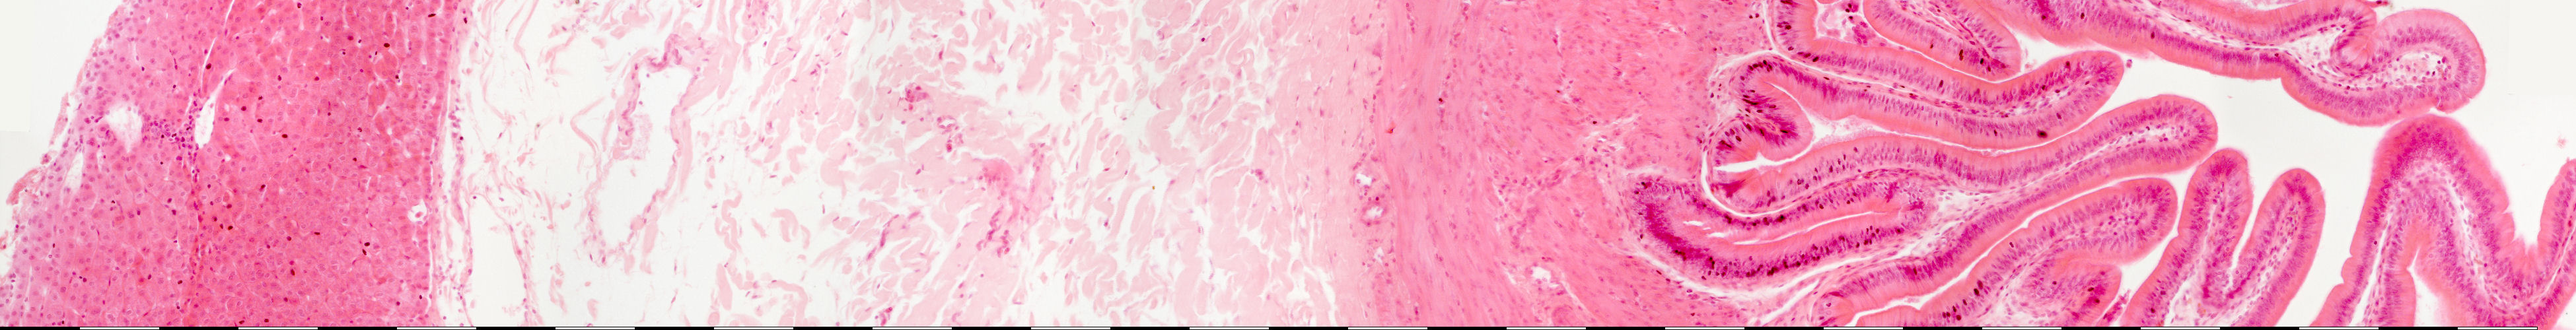

Medium magnification of the gallbladder

Liver

Adventitia

Muscularis externa

Mucosa

Lamina propria

Epithelium

Lumen